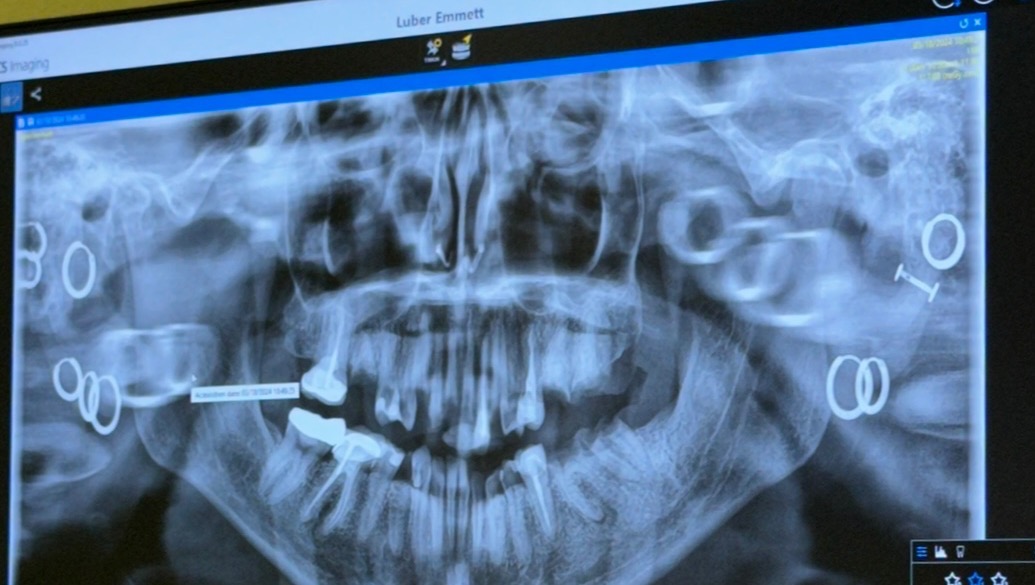

Hi, I’m Emmett. I have a genetic condition called Ehlers Danlos that can cause increased dental decay. On top of that, I went through a severe mental health battle a few years ago and I didn’t get my teeth taken care of during that time because I expected to be dead by 25.

I’m 27 now and I have to get my teeth taken care of before the infection, that I have had in multiple teeth for quite some time, travels to my brain. I need all of my teeth extracted and then either dentures or implants, if I can somehow afford them.

My goal is set for the minimum, which will get my teeth extracted and give me dentures. Ideally I’d like to get implants which would be $18,290 so that my bone loss is minimal, but if I can at least get my dentures that would be a huge help. I have bad credit and don’t qualify for loans, so this is pretty much my last resort. I hate asking here, but I don't want to die of a brain infection before I get the chance to turn 30, and I don’t have any other options.